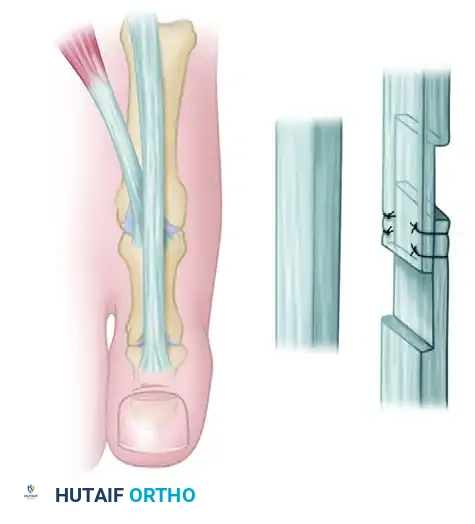

2. Tendon Lengthening and Resection

Correction of the hyperextension deformity at the MTP joint begins with addressing the contracted extrinsic and intrinsic extensor tendons.

- EHL Lengthening: Perform a Z-plasty lengthening of the EHL tendon. A 3-cm coronal Z-plasty is preferred over a sagittal cut, as the coronal plane allows for a smoother gliding surface post-repair and minimizes subcutaneous bulk.

- EHB and EDB Resection: Identify the EHB and EDB tendons, which lie immediately lateral and deep to the EHL and EDL as they approach the MTP joints. Excise a 5- to 8-mm section of both the EHB and EDB. Simple tenotomy is insufficient; a tenectomy prevents spontaneous reconstitution and recurrent contracture.

Clinical Pearl: Do not repair the EHL tendon at this stage. Keep in mind that overlapping the tendons during the final repair is much easier than discovering you have insufficient length when the MTP joint is later pinned or held in a neutral position.

- Pinning Technique: Drive the K-wires retrograde through the distal phalanx so they emerge 2 to 3 mm plantar to the nail bed. Then, drive them proximally across the IP joint into the subchondral bone of the proximal phalanx.

- Elevate the extensor tendon proximally. Perform a resection arthroplasty by removing the distal one-third of the proximal phalanx using a microsaw or bone rongeur.

- Ensure enough bone is resected so that the toe can be held in a neutral position at the PIP joint without any bony impingement.

- Closure and Dermodesis: Hold the joint in the proper position (0 to 15 degrees of flexion). Pass a suture through the skin and tendon, back through the tendon and skin, and tie it in a reverse skin-to-skin mattress configuration. This secures the dermodesis and stabilizes the resection arthroplasty.